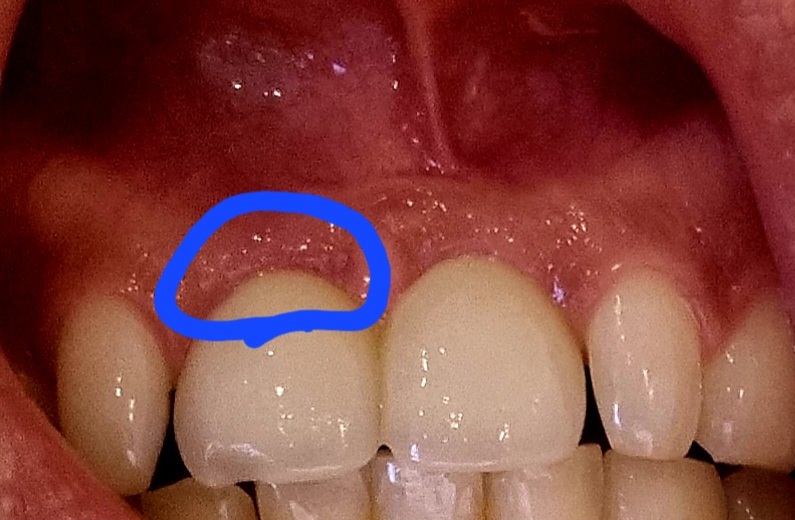

붙혀서 임플란트한 옆 앞니는 눌러도 통증이 없는데 사진상 동그라미친 부분만 통증이 조금 느껴집니다.

• 1번 째 사진